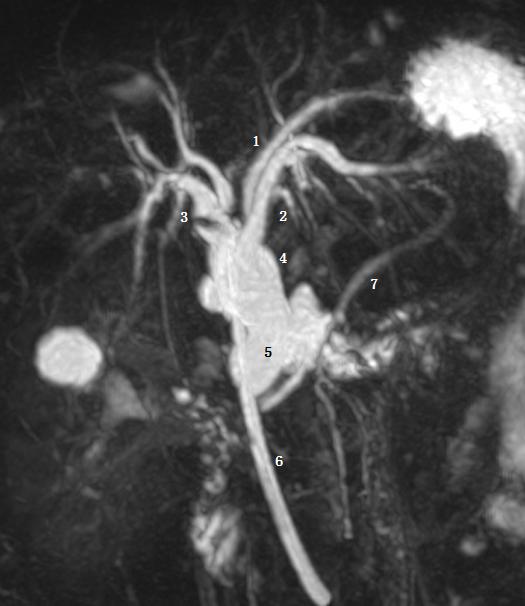

Ⅴ型为副肝管的存在。图示 1 为肝右管,2 为肝左管,3 为副肝管,4 为肝总管,5 为胆囊管,6 为胆总管。

Ⅵ型为 2、3 段分级肝管汇入右肝管或肝总管。图为胆总管末端梗阻 T 管引流术后。图示 1 为 2 段肝管,2 为 3 段肝管,3 为肝右肝管,4 为肝总管,5 为胆总管,6 为 T 型管,7 胰管。